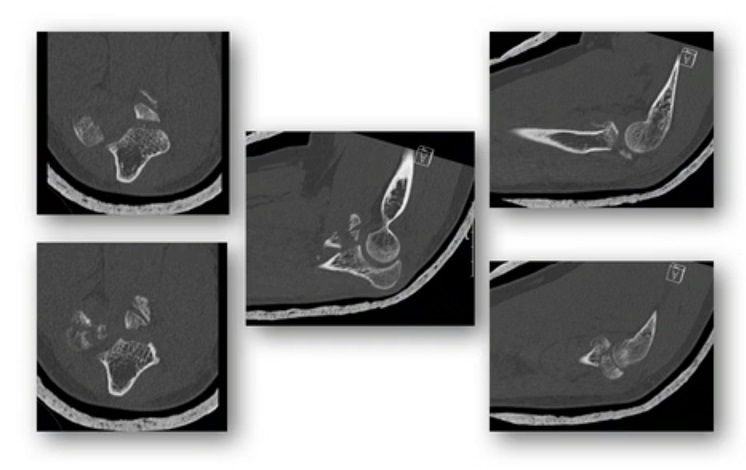

Diagnostischer Mehrwert einer 3-D Schnittbildgebung H. Klauser

Den diagnostischen Mehrwert einer 3-D Schnittbildgebung kennenzulernen